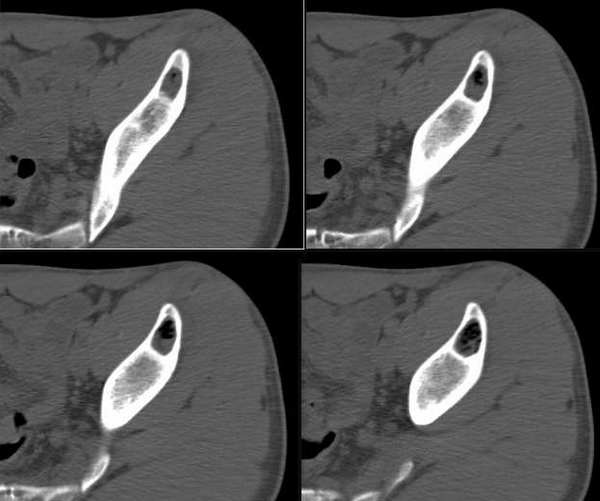

男性,19,左侧髋部疼痛两周。病变ct值有软组织及脂肪密度影。

影像表现:左侧髂骨内卵圆形囊性低密度灶,病灶内为脂肪密度及软组织密度;周围骨质似有轻度硬化带,局部骨皮质完整、光滑;未见骨膜下新生骨。

意见:骨良性病变,考虑为骨脂肪瘤。

骨肿瘤或者肿瘤样变的病灶中出现脂肪密度的有:骨脂肪瘤,骨脂肪肉瘤,骨囊肿等

骨囊肿内多为液性密度,也可含有少量胆固醇成分或者肉芽组织成分,本例病灶内脂肪成分较多,不含液性成分;脂肪肉瘤病灶为恶性浸润征象多见,也可见有钙化征象。

定位:左髂骨

征象:囊状低密度病灶,边缘清楚、光整,有薄层硬化边缘,其内密度不均,可见液平面。无明显骨膜增生和软组织异常。

定性:良性

1、骨囊肿:多见于20岁以下青少年,病变为单囊或多囊,其内通常可见骨性或软组织间隔,骨折时可有液性密度影,也可含少量脂质,应首先考虑。

2、动脉瘤样骨囊肿:好发于年轻人,病灶一般膨胀明显,密度不均,包括软组织影、液体密度影,偶尔有斑片状钙化影,不能排除。

3、骨脂肪瘤:少见,多见于中年人,病灶内常有钙化或骨化影,因伴有其他不同成分使得脂肪含量变化较大,一般没有液体影像,可能性不大。

左侧髂骨内卵圆形囊性低密度灶,病灶内为脂肪密度及软组织密度;周围骨质似有轻度硬化带,局部骨皮质完整、光滑;未见骨膜下新生骨。图像上髂骨周围软组织未见确切异常。

考虑骨良性病变,骨脂肪瘤可能性大。其他待排。